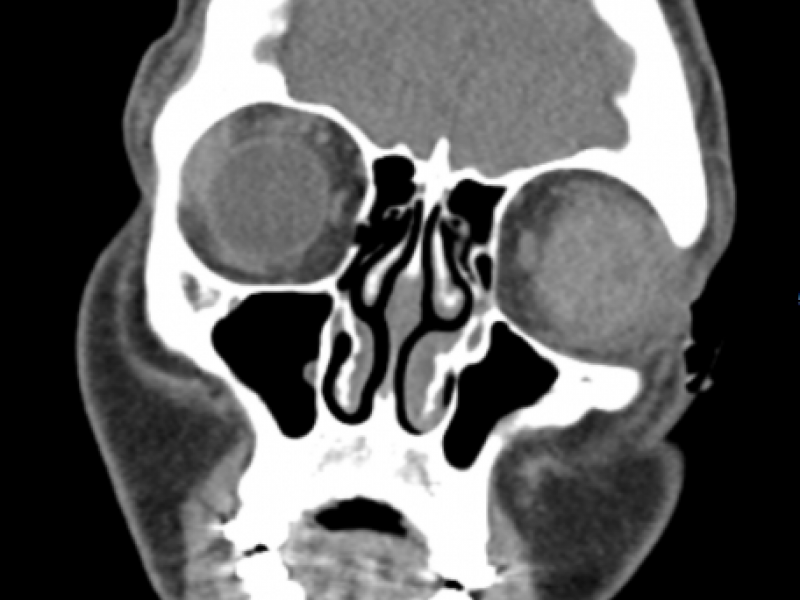

A 59 yo male presented to the Emergency Department after a